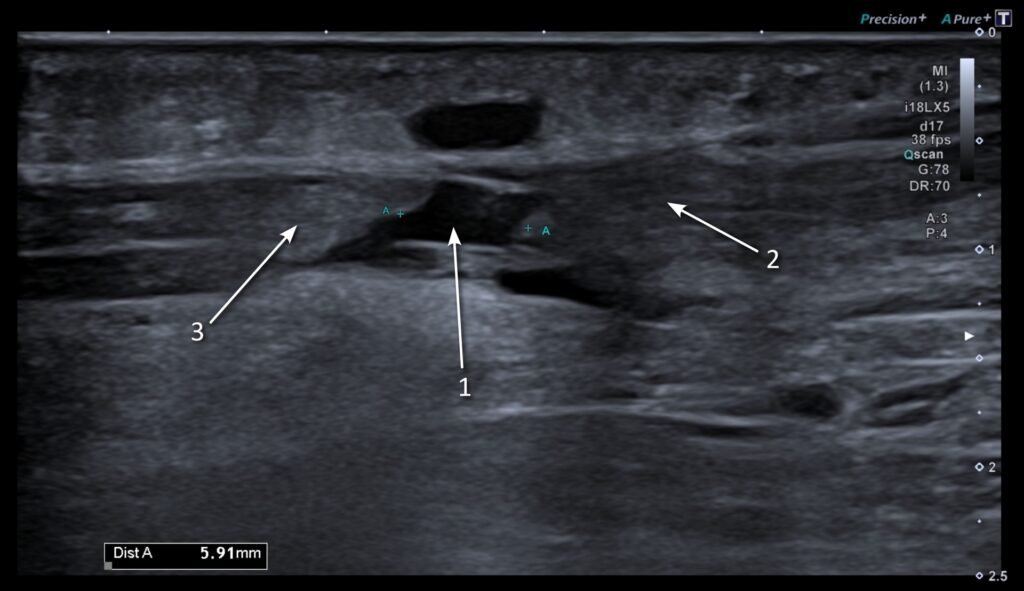

The tendons around the ankle are enveloped by a tendon sheath. This contains a sliver of synovial fluid, a lubricant facilitating the gliding of the tendons during ankle motion. Tenosynovitis is when the tendon sheath itself gets inflamed. On ultrasound, this is seen as a build-up of fluid, thickening and increased blood flow (see Figure 4).